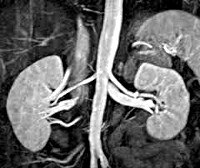

Гормональную активность опухоли надпочечников можно оценить, используя селективную надпочечниковую флебографию - рентгенконтрастную катетеризацию надпочечниковых вен с последующим забором крови и определением в ней уровня гормонов. Исследование противопоказано при феохромоцитоме, может спровоцировать развитие криза. Размеры и локализацию опухоли надпочечников, наличие отдаленных метастазов оценивают по результатам УЗИ надпочечников, КТ или МРТ. Эти диагностические методы позволяют выявить опухоли- инциденталомы диаметром от 0,5 до 6.